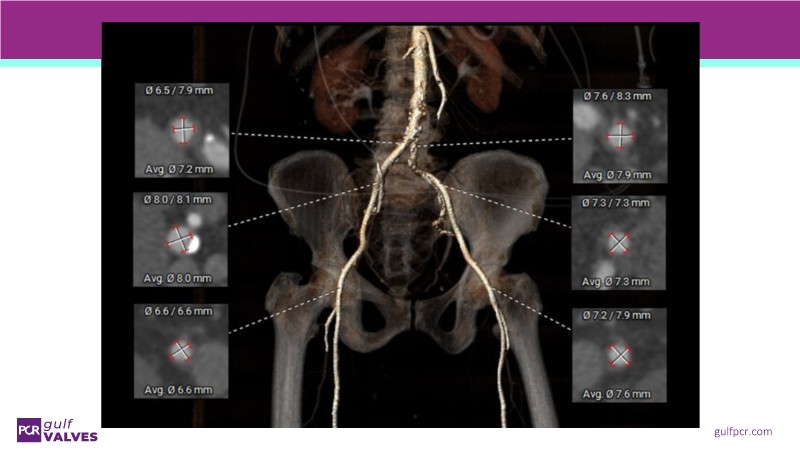

Join this comprehensive session to explore the Myval transcatheter heart valve series, featuring the latest clinical updates from two large randomized controlled trials—Landmark and Compare TAVI. Learn from real-world experiences, including recorded cases, and understand how these innovations translate to complex patient demographics in daily TAVI practice.